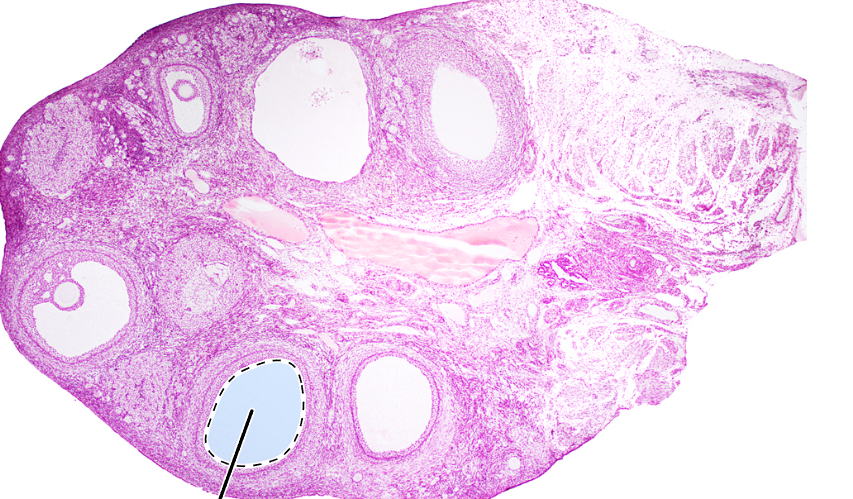

ovary (sagittal section)

antrum

corona radiata

zona pellucida

oocyte